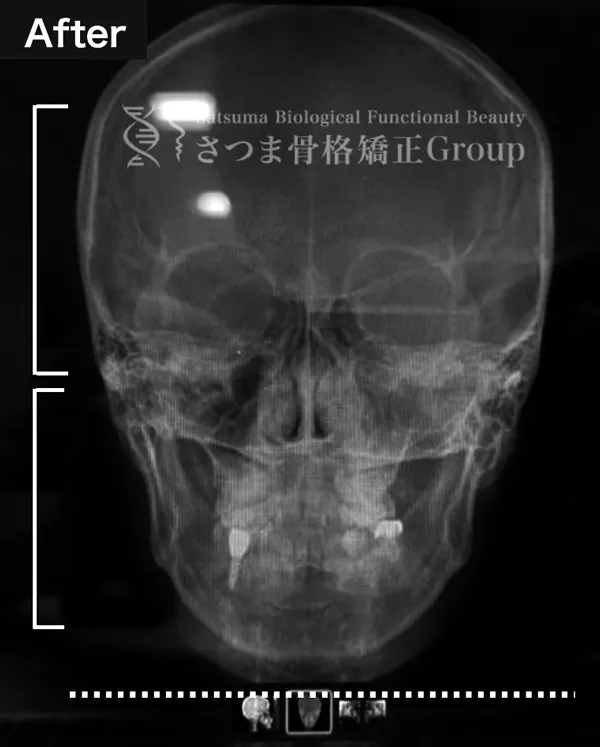

AFTER

下顎の正中誘導

頚椎の斜頸矯正

中顔面の短縮

Midline correction of the mandible

Correction of cervical spine torticollis

Shortening of the midface

BEFORE

軽度の顎変形症あり

下顎の左方シフト

頚椎の斜頸

中顔面の滑落

Mild jaw deformity present

Leftward shift of the mandible

Cervical spine torticollis

Sagging of the midface